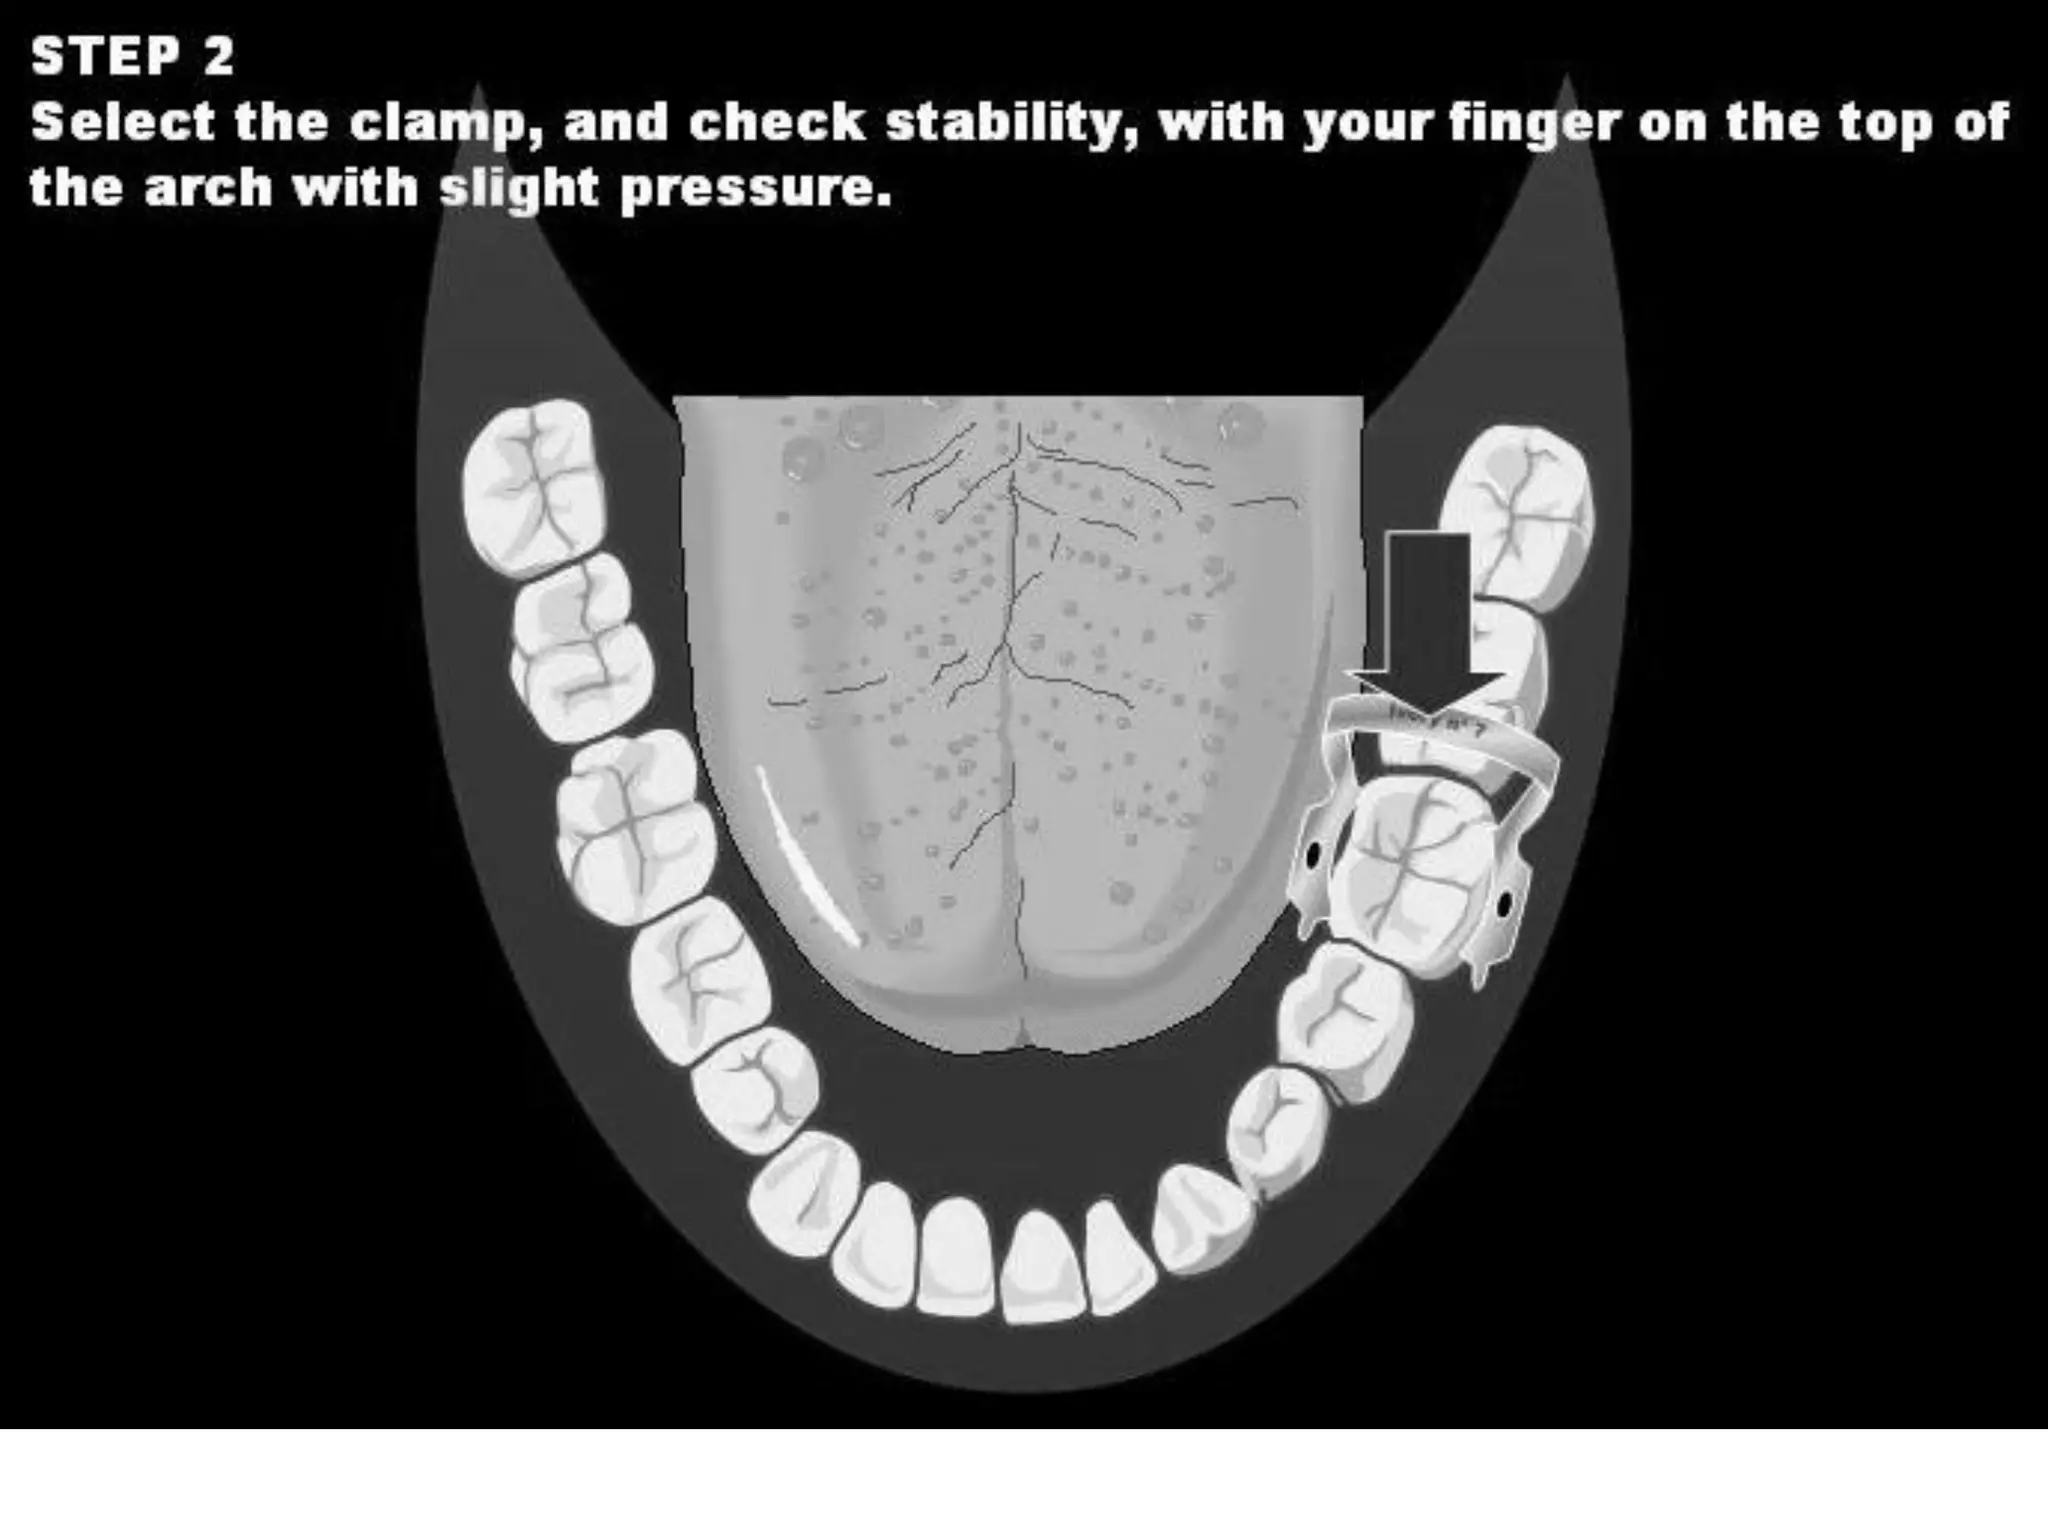

This document discusses the materials and components used for rubber dam isolation in dentistry. It describes the different types of rubber dam materials including color options and napkins to absorb moisture. It also outlines the tools needed such as punches to make holes, templates and stamps to guide hole placement, clamps to secure the dam, and other accessories like wedges and lubricant. Finally, it provides guidance on punching holes for different types of teeth and properly placing clamps in the rubber dam.